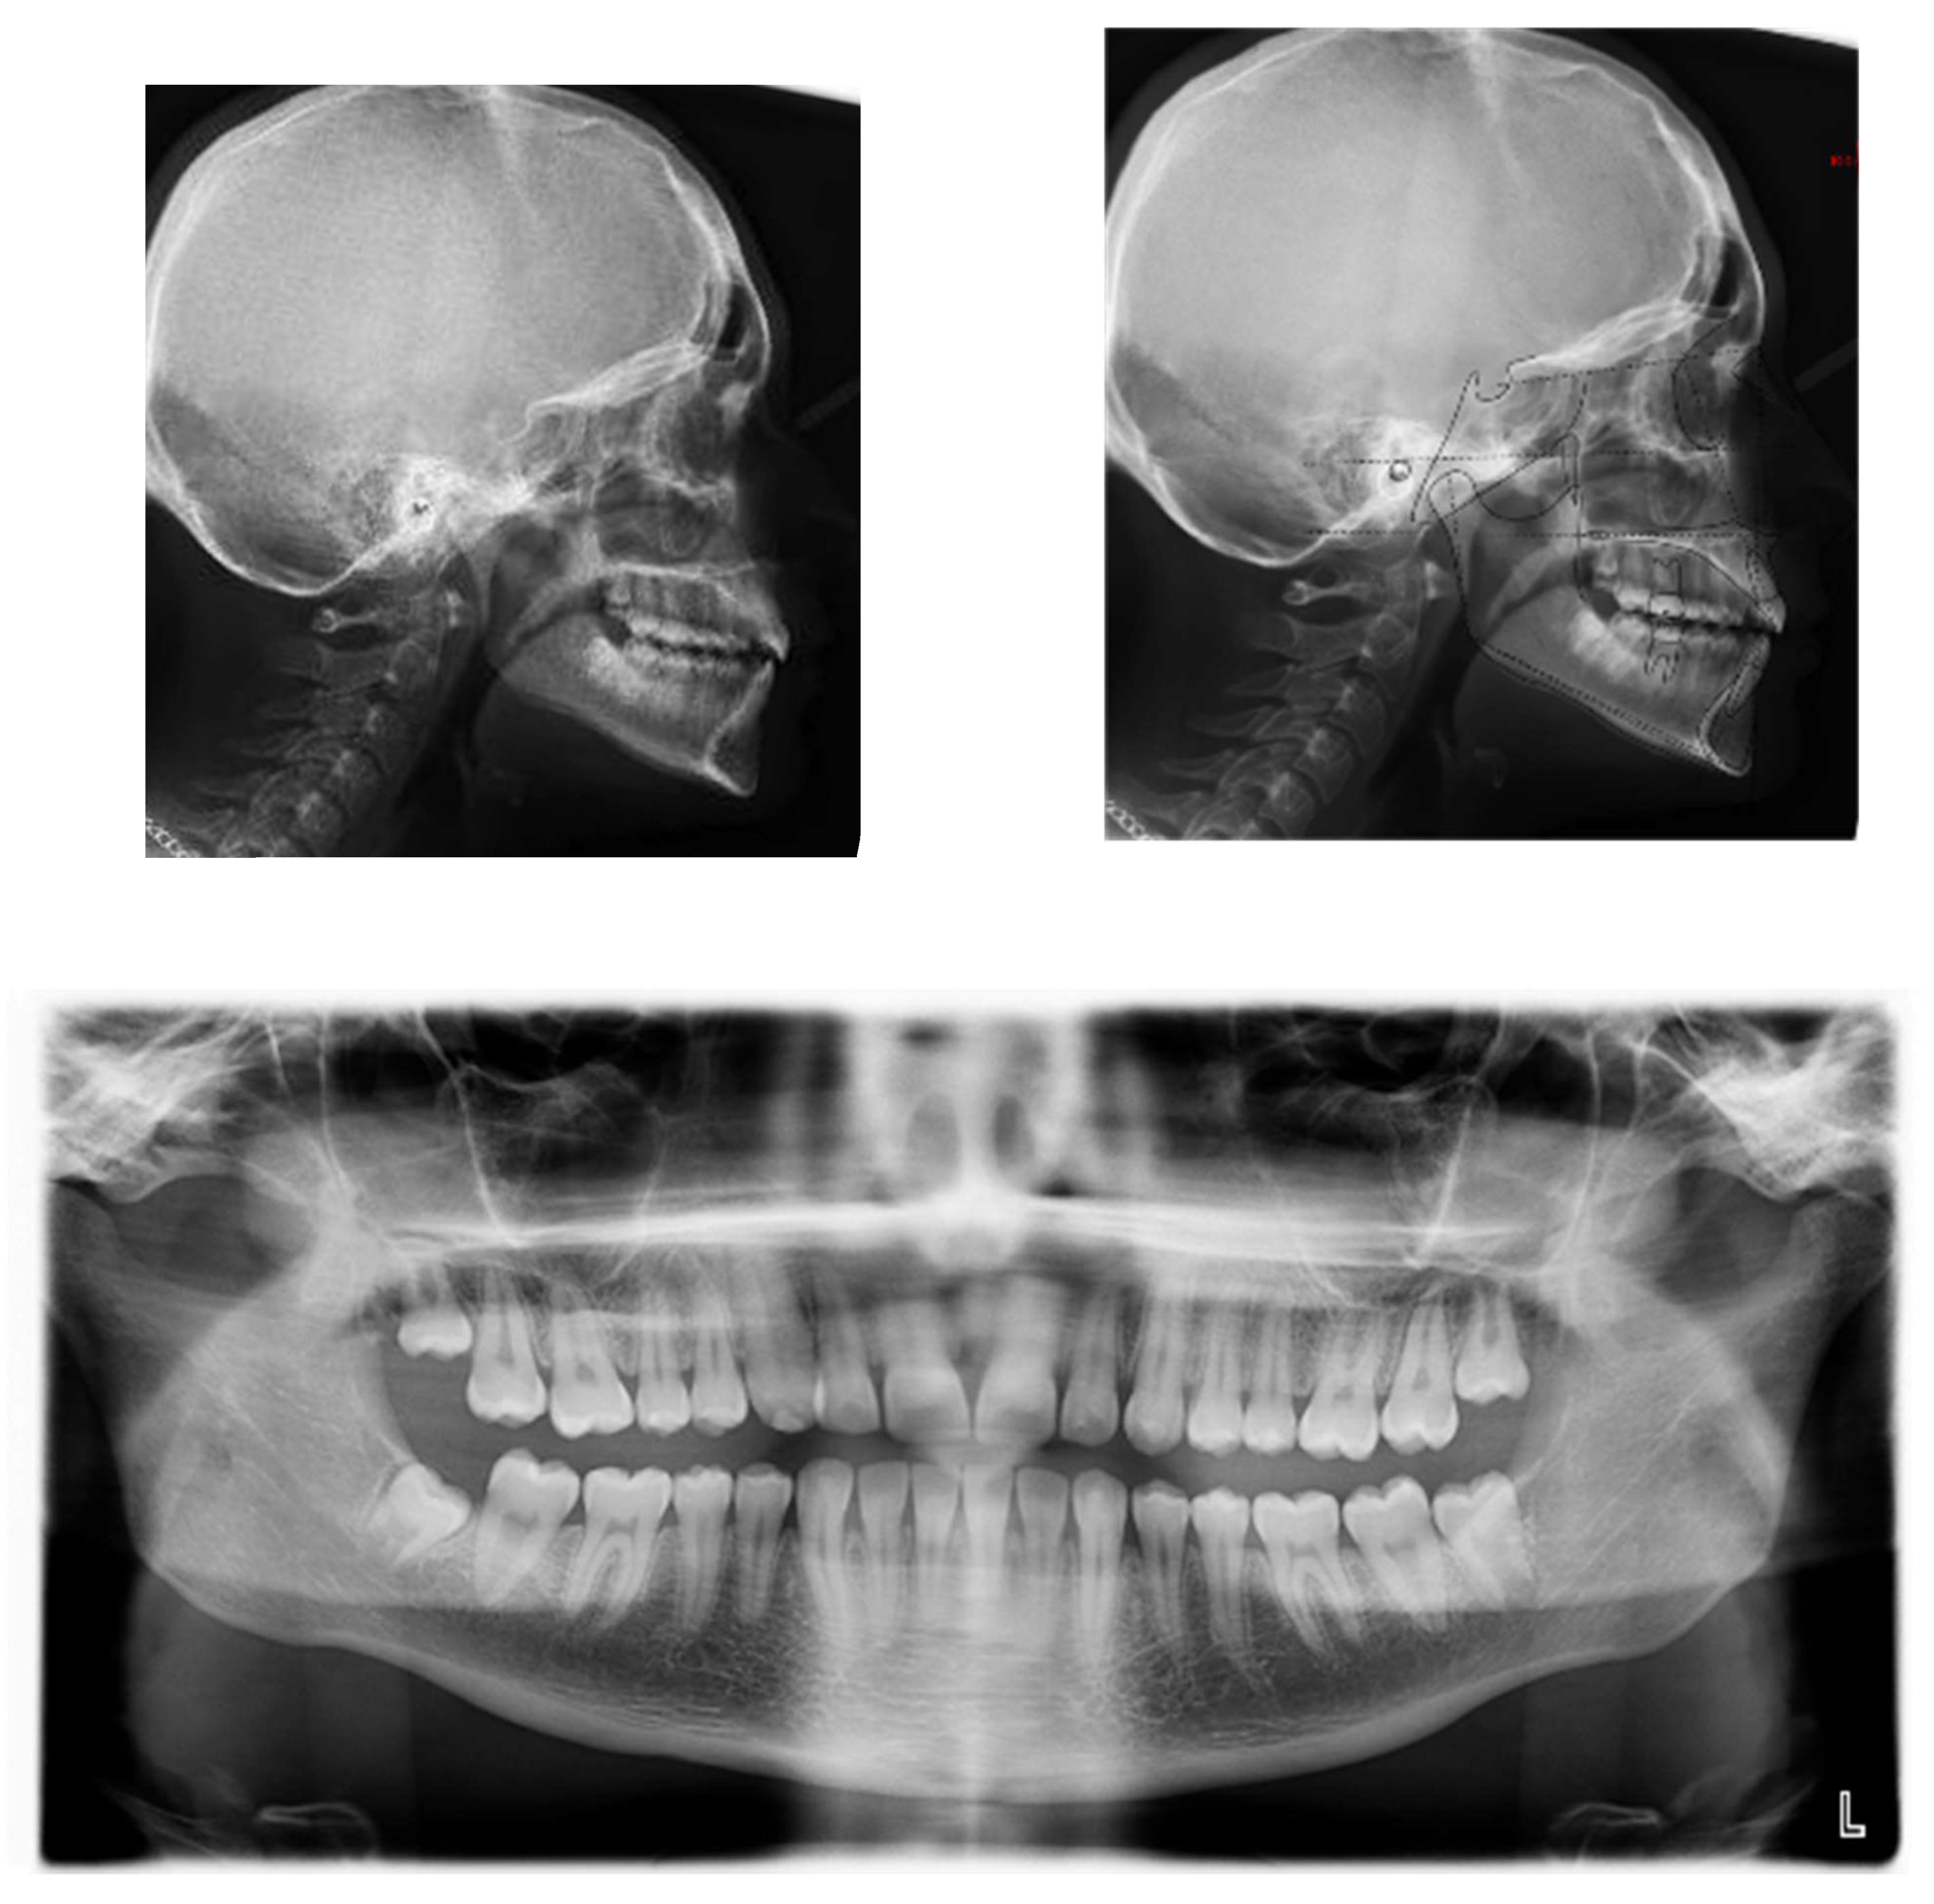

A 17-year-old female patient came for an observation in good general and oral health without any significant pathologies.

The chief complaint of the patient was the absence of a permanent maxillary canine. Her face, from a frontal view, appeared well-proportioned in the three-thirds with facial symmetry.

From a lateral view, the profile appeared straight and a normal nasolabial angle, labiomental sulcus, and lip competence was represented. The initial records were collected and X-rays were taken (Figure 1).

A 17-year-old female with dentoskeletal Class I with an impacted upper right canine before treatment.

Intraorally, the patient had Class I molar and canine relation on both sides, along with normal overbite, overjet, and the retention of the deciduous canine.

The cephalometric analysis showed a skeletal Class I (ANPg +1.7°) with a good proportion of the maxillaries (SNA 84°; SNB 82.3°) in a normo-divergent vertical pattern (SN^Go-Gn = 32.8°) and a good inclination of the upper and lower teeth, respectively (I/ANS-PNS 116.2°; i/GoGn 91.6°) (Table 1).

The panoramic X-ray showed unilateral permanent canine displacement in sector four with an alpha angle of more than 53° degrees according to the Ericson and Kurol classification (Figure 2).

Pre-treatment panoramic X-ray with the evaluation of alpha angle and sector according to the Ericson and Kurol classification.